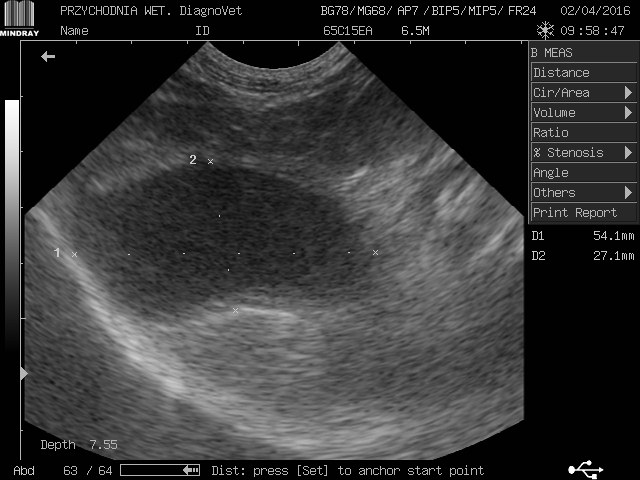

gracja1 Posted August 24, 2017 Posted August 24, 2017 Witam moja ukochana psinka gracja z wyników usg jest w bardzo kiepskim stanie nerki a praktycznie ich brak kwalifikują ja tylko do eutanazji jeżdżę od weta do weta i wszędzie żadnej pomocy.Gracja to piesek mieszany średniej wielkości trafiła do nas w ubiegłym roku ma zaledwie 2 lata.O chorych nerkach dowiedzieliśmy sie tydzień po przyjeździe jak do nas trafiła od początku objawy były ciągłe pragnienie wody i częstomocz decyzja tylko jedna jedziemy do weterynarza tam stwierdzono ze to zwykłe przeziębienie minęło parę dni brak poprawy u pieska powrót do weterynarza.Kazano zrobić badanie krwi moczu i wyszło kreatynina i mocznik podwyższony skierowano mnie na badanie usg tam potwierdziło chore nerki liczne cysty wokół diagnoza eutanazja natychmiastowa.Nie poddałam się minął rok z gracja od tamtej pory jest zemną bawi się biega kocha mnie nad życie lecz od paru dni dziwnie zaczęła się zachowywać jest osowiała mało zjada pije wodę wzięłam ja do weterynarza po diagnozie weterynarze są w szoku ze moja gracja żyję a na wieść o tym we dwoje zaczęli usg i to co zobaczyli to praktycznie brak nerek jedynie cysty do tej pory niewiadomo co tak naprawdę trzyma psa przy życiu i dziwią się ze on chodzi i biega w takim stanie a ja słyszę tylko w kółko pies do usypania zero szans zero leków absolutnie żadnej inicjatywy ze strony lekarza czy to normalnie dlatego jestem tutaj i opisuje swoja sytuacje a gracja leży przy mnie i nikt niepotrafi pomóc.Przesyłam skan usg krótko po przyjeździe gracji do mnie i pierwsze usg proszę o jakieś wskazówki do kogo jechać z kim porozmawiać bo siedzę i tony łez wylewam.Wyniki krwi z dnia 22.08.2017 Kreatynina 8.70mg/dl ,mocznik 300mg/dl 1 Quote